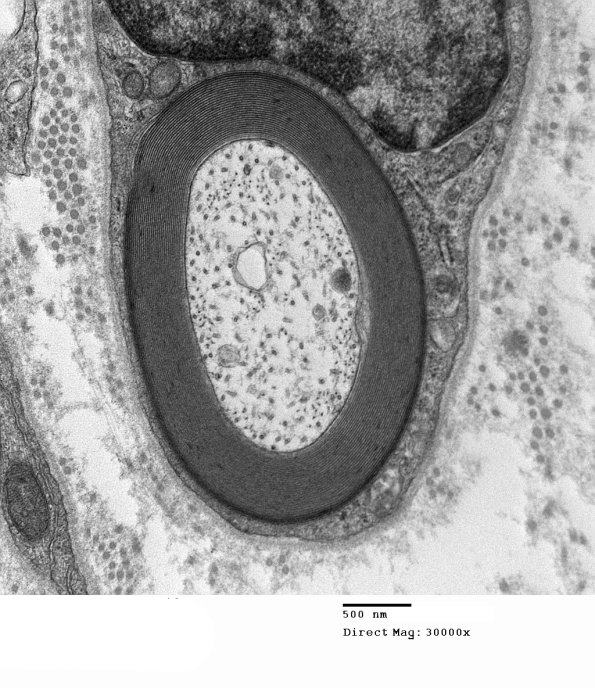

0A3-5 These are electron micrographs of a small myelinated sural nerve axon with several magnifications of its normal myelin sheath. Myelin periodicity is normal from one lamella to another irrespective of its adaxonal (the inner surface of the myelin sheath, closest to the axon) or abaxonal (the outer surface furthest from the axon) location. (electron micrographs)